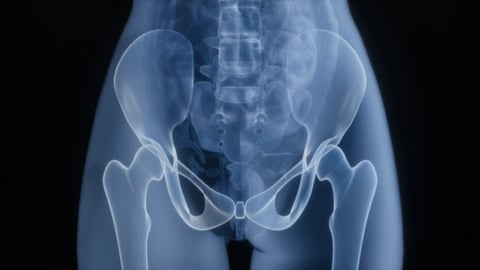

An image of a person’s pelvic X-ray showing the hip bones, spine, and upper leg bones.

43% of Hip Replacement operations are done in people aged 50 to 69 years old.Rohit Choudhari/ Unsplash